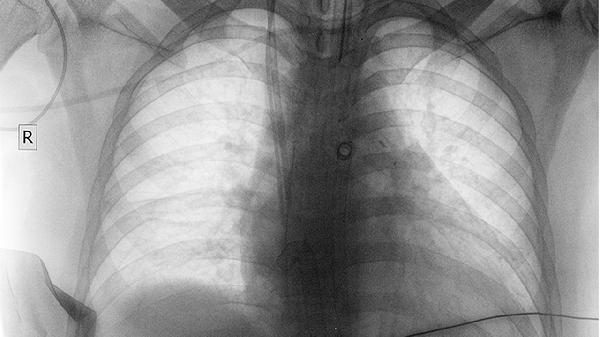

4、肺癌

部分肺癌患者可遵医嘱使用该药辅助治疗,尤其对放化疗期间骨髓抑制的改善可能有一定效果。肺癌患者多见咳嗽、咯血、胸痛等症状。医生可能根据病理类型联合使用吉非替尼片、贝伐珠单抗注射液等药物。